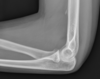

Condroblastoma da escápula